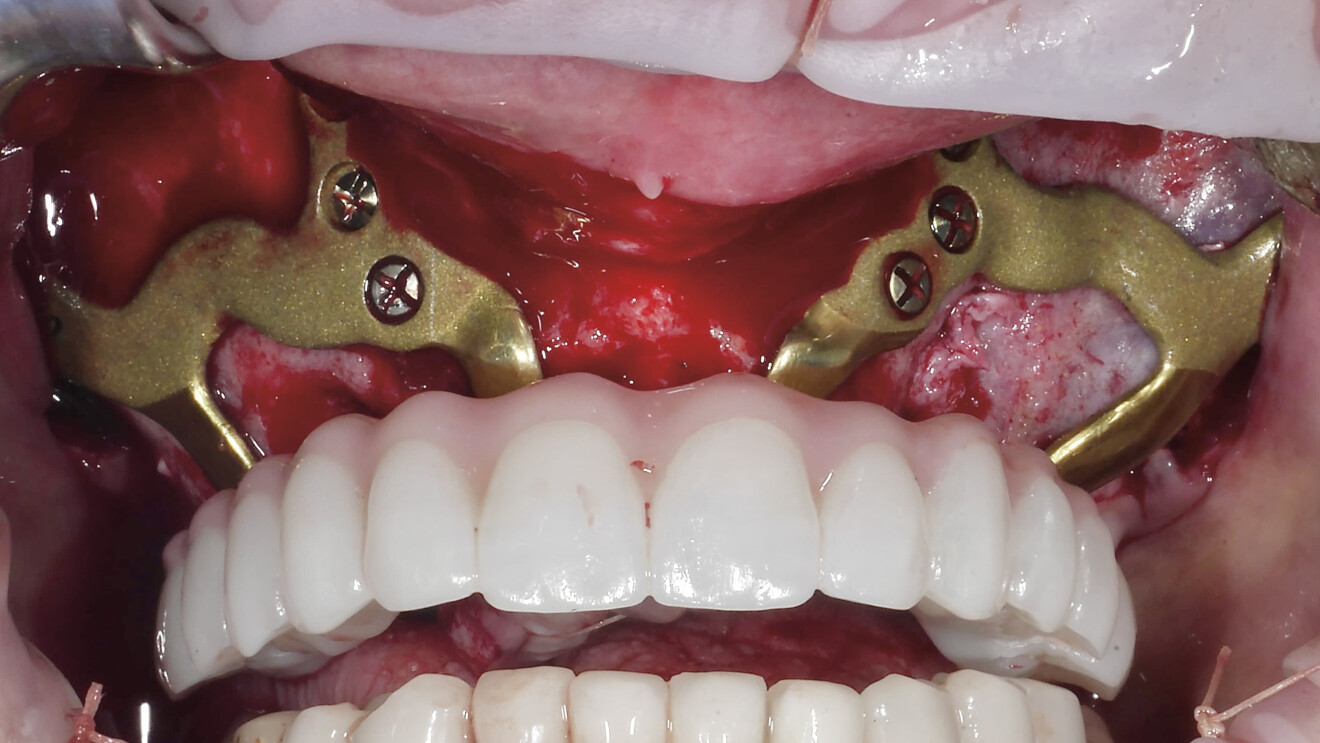

Fig. 2a : Photographie endobuccale d’ISP maxillaire.